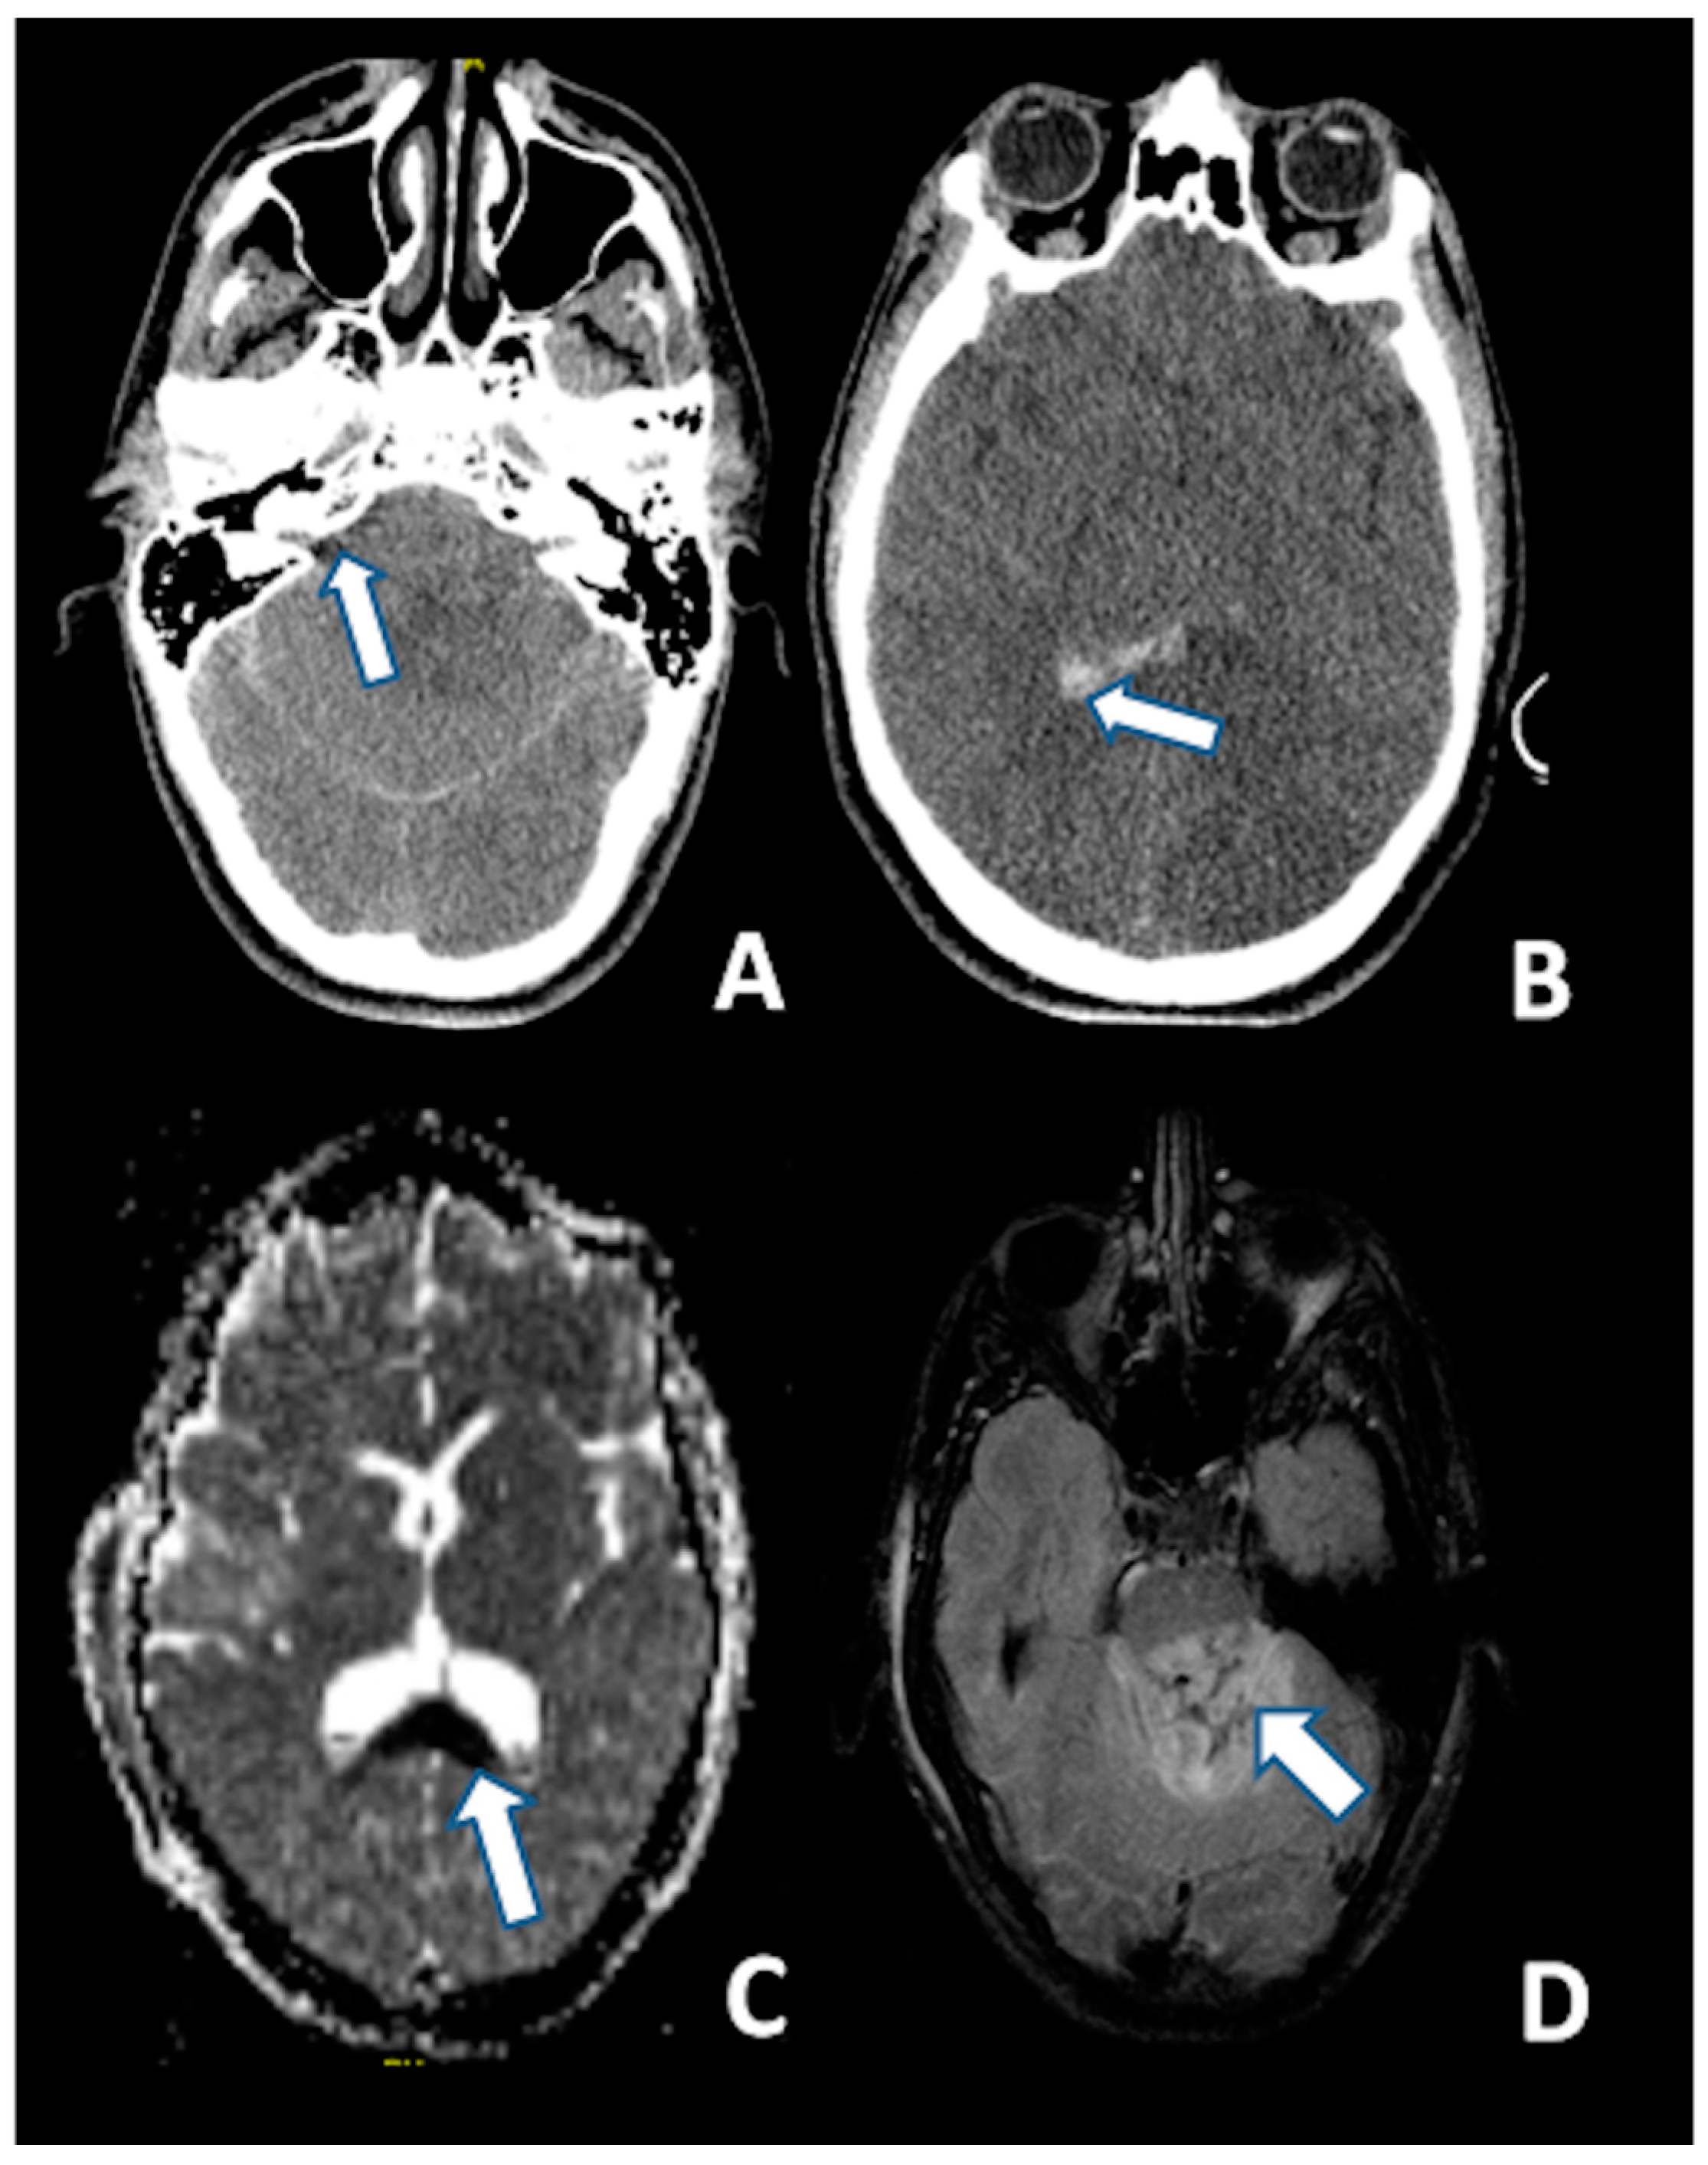

T2-weighted and, particularly FLAIR sequences, provide good visualization of non-hemorrhagic parenchymal lesions, but DWI has a greater sensitivity for identifying DAI as hyperintense lesions (Figure 3) [134].